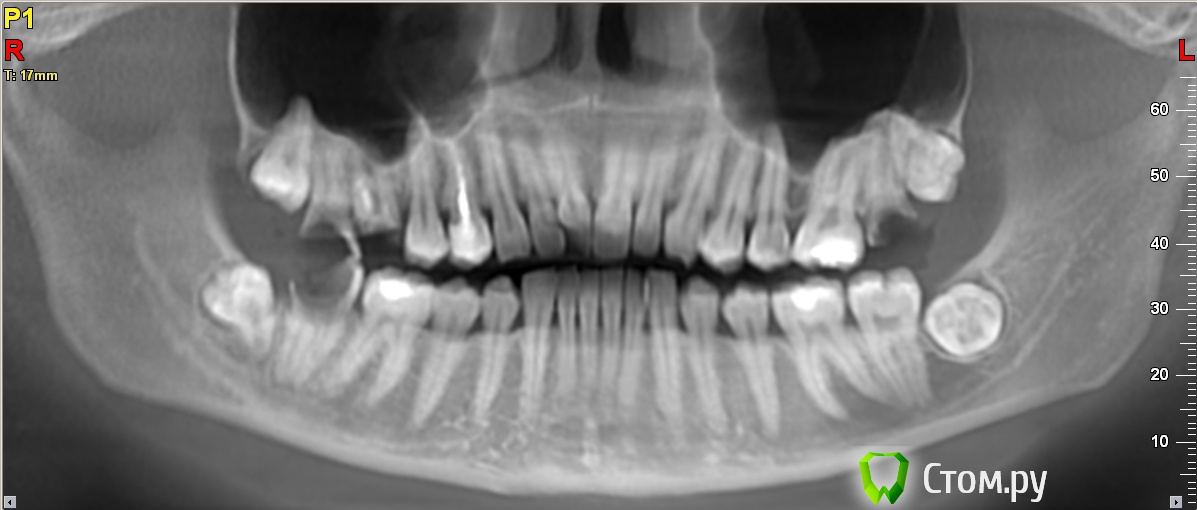

Flygirl Опубликовано 3 марта, 2014 Поделиться Опубликовано 3 марта, 2014 Добрый день!) Хотелось бы услышать ваше мнение относительно моей челюсти. Больше всего меня интересует 7-ка слева сверху - удалять или можно попробовать восстановить? Семёрку снизу (правая сторона) уже удалили - ждём заживления и имплант. Слева сверху 7-ка на стадии установки культеевой вкладки, а 6-ку приговорили на удаление. Что скажете, все-ли верно делаем?) И есть-ли еще какие-то проблемы?И еще вопросик - можно-ли при удалении 6-ки сверху справа использовать одномоментную установку импланта или ждать заживления?Спасибо заранее за ответы Ссылка на комментарий

Acidrocker Опубликовано 3 марта, 2014 Поделиться Опубликовано 3 марта, 2014 Здравствуйте. Семерки (не совсем понял, какая вас интересует на данный момент) можно попытаться восстановить, зависит от степени разрушения твердых тканей зуба. Перед имплантацией в области 6 могут потребоваться дополнительные мероприятия по наращиванию кости. Нижние зубы "мудрости" нужно удалять. Ссылка на комментарий

Flygirl Опубликовано 3 марта, 2014 Автор Поделиться Опубликовано 3 марта, 2014 Здравствуйте. Семерки (не совсем понял, какая вас интересует на данный момент) можно попытаться восстановить, зависит от степени разрушения твердых тканей зуба. Перед имплантацией в области 6 могут потребоваться дополнительные мероприятия по наращиванию кости. Нижние зубы "мудрости" нужно удалятьСпасибо большое за ответ) семёрка меня интересует на данный момент та, которая если смотреть на снимок - с правой стороны (там где один разрушенный зуб)Вот как чувствовала, что придётся наращивать кость и очень этого боялась то есть рассчитывать на удаление и сразу установку импланта точно не стоит?Про зубы мудрости догадывалась, но врач говорит, что они так лежат, что могут и вообще никогда не вылезти и не беспокоить...ну я об этом наверное буду думать после проведения всех работ с разрушенными зубами... Ссылка на комментарий